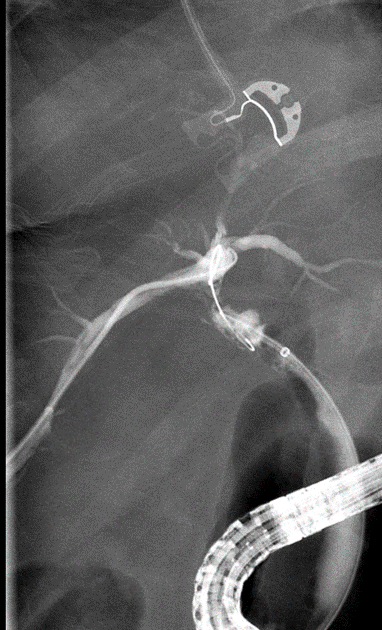

Following this, the patient experienced continued abdominal pain and bile in her JP drain 2 days post-operatively. An ERCP was performed (see cholangiogram in Figure 1) and a stent was placed into the CBD. It is evident from this cholangiogram that the right posterior sectional duct is not filling, consistent with either a Strasberg type B or C injury.

Figure 1. ERCP cholangiogram performed when bilious drainage was visualized post cholecystectomy from the JP drain in the gallbladder fossa.